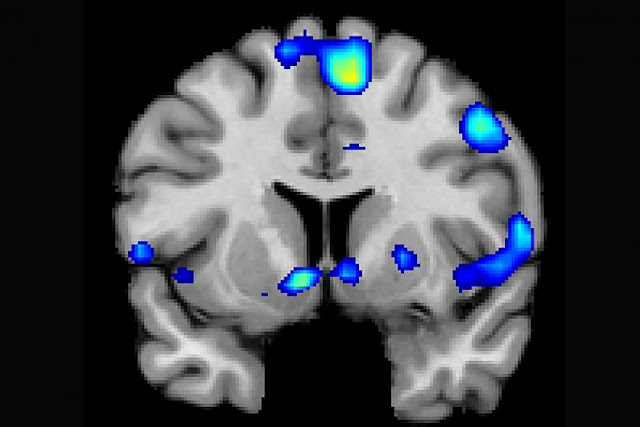

| fMRI scans recorded brain activity as devoutly religious study participants read quotes from spiritual leaders or watched religious imagery. University of Utah Health Sciences. |

| Several brain regions become active when devoutly religious study participants reported having a spiritual experience, including a reward circuit, the nucleus accumbens. Credit: Jeffrey Anderson |

Religious and spiritual experiences activate the brain’s reward circuits in a similar way to love, gambling, and music, a new study finds. Researchers used fMRI scans to look at the brains of 19 devout Mormons as they engaged in an experience described as "feeling the Spirit." This feeling was reproducibly associated with activation in nucleus accumbens, a critical region for processing reward and pleasure in the brain.

Anderson: In a group of devout Mormons, a spiritual experience they describe as "feeling the Spirit" is associated with activation in a reproducible network of brain regions. These regions include the nucleus accumbens, a critical region for processing reward and pleasure in the brain. We also found activation in attentions associated with perception of salience or novelty in the brain, and in regions that are associated with focused attention.

In one experiment, we had individuals press a button while watching audiovisual stimuli when they felt peak spiritual feelings. Activation in the nucleus accumbens spiked 1-3 seconds before they pressed the button, suggesting that there is a close relationship between spiritual feelings and brain reward activation. The centrality of reward in brain responses to spiritual feelings suggest that one view of religious training might align with classical conditioning, where association of positive feedback, music, and social rewards with religious beliefs or doctrines may lead to these doctrines becoming intrinsically rewarding. These same mechanisms may help explain attachment to religious leaders and ideals.